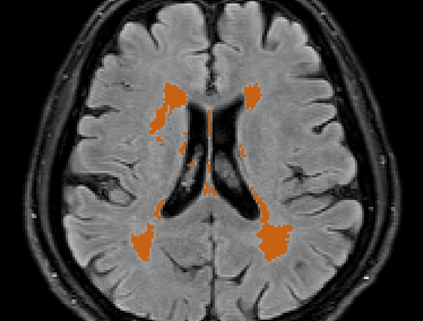

Brain atrophy and white matter hyperintensity (WMH) are critical neuroimaging features for ascertaining brain injury in cerebrovascular disease and multiple sclerosis. Automated segmentation and quantification is desirable but existing methods require high-resolution MRI with good signal-to-noise ratio (SNR). This precludes application to clinical and low-field portable MRI (pMRI) scans, thus hampering large-scale tracking of atrophy and WMH progression, especially in underserved areas where pMRI has huge potential. Here we present a method that segments white matter hyperintensity and 36 brain regions from scans of any resolution and contrast (including pMRI) without retraining. We show results on six public datasets and on a private dataset with paired high- and low-field scans (3T and 64mT), where we attain strong correlation between the WMH ($\rho$=.85) and hippocampal volumes (r=.89) estimated at both fields. Our method is publicly available as part of FreeSurfer, at: http://surfer.nmr.mgh.harvard.edu/fswiki/WMH-SynthSeg.